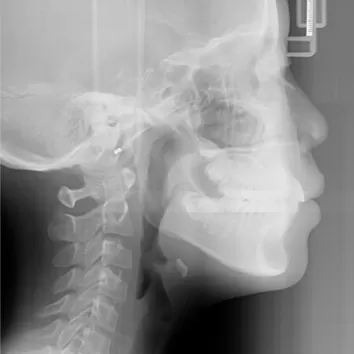

Rayons X avant le traitement

[Radiographie panoramique/Céphalogramme latéral]